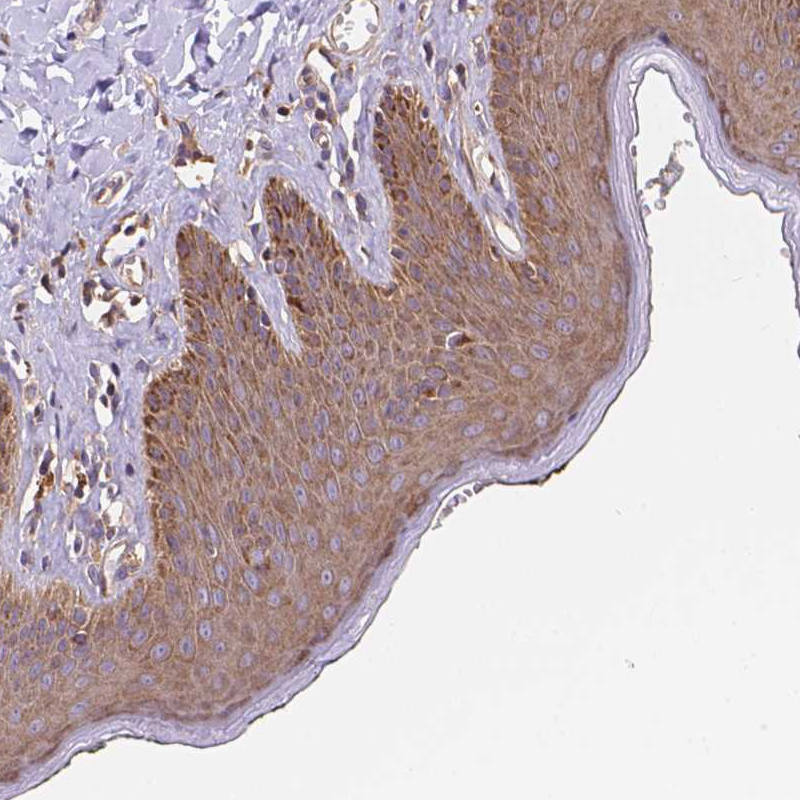

Immunohistochemical staining of human tonsil shows strong cytoplasmic and memranous positivity in germinal center cells.